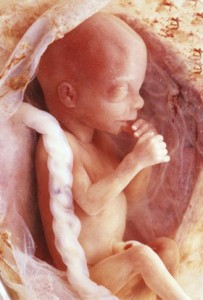

Фото плода на 13 тижні вагітності

Дитина росте як на дріжджах. На 13 тижні вагітності розмір плода вже досягає 7-8 сантиметрів, важить близько 14-20 грам.

Дивно, що до такого терміну у крихти вже пройшла закладка всіх молочних зубів, залишається лише чекати моменту, коли вони вийдуть на світло. Крім того, підшлункова залоза малюка вже почала вироблення 1-го інсуліну. При цьому починає швидко рости тулуб, і незабаром голова не стане великою. Хоча розмір плода малесенький, на даному етапі його руху майже без перерв. Це потрібно для гарного розвитку кінцівок і мускулатури. Кроха відпочиває тільки під час недовгого сну.

Зараз відбувається формування м'язів і кісткової тканини дитини. Прогрес з'являється і в травній системі: починають утворюватися важливі ворсинки, які беруть участь в процесі переробки продукції. На такому терміні здійснюється закладка голосового апарату, а зовнішність малюка знаходить характерні риси.

Тринадцятий тиждень вагітності вказує на 11-тижневий вік плоду. Його вага - близько 8 г, зріст - близько 8 см. Плід і його розташування можна розглянути на знімку УЗД.

Розвиток дитини не зупиняється ні на секунду. На даному етапі йде інтенсивне формування кісткової системи - зміцнюються кістки черепа, закладаються ребра, з'являються зачатки зубів. А ще на пальцях з'являється унікальний малюнок!

Всі молочні зубчики у плода сформовані, повіки ще закриті, тільки починають закладатися тканини, з яких потім почнуть формуватися кісточки. Більш чітко вимальовуються подбородочек і носик.

У кишечнику, який вклався в черевній порожнині, формуються, важливі для перетравлення їжі, ворсинки, а підшлункова залоза вже виробляє інсулін.

Плацента зараз для плода джерело їжі і кисню і готова почати продукувати гормони естріол і прогестерон.

Довжина плоду становить всього 6-8 мм, а вага - 14-20 гр, тому фото животиків на 13 тижні вагітності показують практично абсолютно звичайний жіночий живіт, у деяких, навіть без найменшої ознаки вагітності або ж невелику пружну округлість.